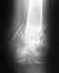

Re: перелом внутренней лодыжки левой голени, левой м/берцовой кости с подвывихом стопы

Действительно, взаимоотношения в суставе требуют восстановления. Добраться к нам проблем не составляет, привозят не то что ходящих на костылях, а и лежачих. Бывает, за тысячи км.